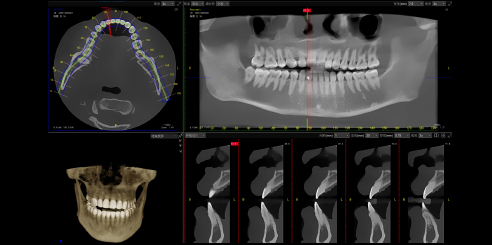

To begin with, the Dental CBCT by LargeV delivers advanced AI-powered 3D imaging and panoramic X-ray designed for accurate dental diagnostics and treatment planning.

It ensures detailed visualization of oral structures while keeping radiation exposure low and image quality high.

The LargeV CBCT supports CT, CEPH, and panoramic imaging in one compact system.

It delivers sharp, high-contrast images that reveal every dental structure with exceptional clarity.

The system achieves image resolutions up to 2.0 lp/mm with a voxel size range of 0.05 – 0.25 mm.

Its 0.5 mm small focus tube guarantees smooth, stable, and reliable scans.

Resolution up to 2.0lp/mm, voxel size of 0.25~0.05 mm optional.

Furthermore, Panoramic Images are Reconstructed from 3D Dental CBCT data for clearer visualization

Additionally, the system provides three flexible scan modes to match clinical needs. Multiple focus layers in panoramic imaging fit each patient’s dental arch perfectly.

360°scan and 800 frame images with unique CT algorithms